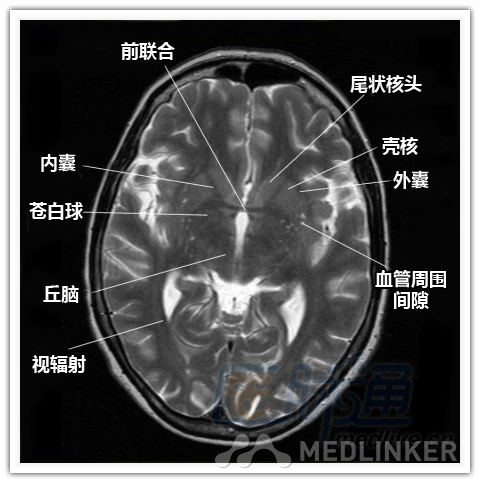

本文将对不同横断位的脑部MRI图像进行标示,主要讲解内容是脑部基本解剖。脑部横断位解剖,尤其是内囊层面的影像学解剖一直是一大重点,一起来学习一下。 现在是内囊层面了,同志们准备好了吗? 本文转载自医脉通。 声明:本文转载是出于提供更多信息以参考使用或学习、交流之目的,不用于商业用途。转载无意侵犯版权,如转载文章涉及您的权益等问题,请作者速来告知,我们将尽快做删除处理。